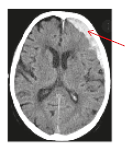

• Contusion is a “bruise” that may cause tissue damage and bleeding (Figure 2).

Contusion or bruising in the brain

Figure 2